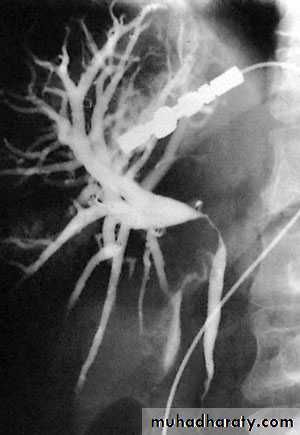

NORMAL ERCP

Endoscopic retrograde cholangiopancreatographydemonstrating stone obstructing the common bile duct (arrow